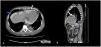

Regardless improvement of infectious parameters, the patient evolved with hypotension and peritoneal drainage with daily variable ultrafiltration volumes was observed. Echocardiography was performed revealing de novo pericardial effusion with signs of cardiac tamponade and, on day twenty-five after the surgery, the patient underwent evacuating pericardiocentesis. Evaluation of pericardial fluid for glucose revealed a concentration of 2000mg/dL, superimposed with that of peritoneal fluid, which led to a diagnosis of an iatrogenic peritoneal–pericardial leakage after pericardiocentesis. After two days of PD suspension the patient has restarted the technique, but extremely variable peritoneal ultrafiltration volumes persisted. Revaluating echocardiography revealed recrudescence of severe pericardial effusion. A CT peritoneography with iodinate contrast infusion through the peritoneum was performed and confirmed peritoneal–pericardial leakage (Fig. 1).

The presentation of our patient was exceptional, as he presented with variable ultra-filtration volumes with true ultrafiltration failure rarely observed. Biochemical analysis with glucose measurement of the pericardial fluid and radiologic investigations such as peritoneography with injection of iodinated contrast by CT or by magnetic resonance and peritoneal scintigraphy allow for a definitive diagnosis, as was the case of our patient.5